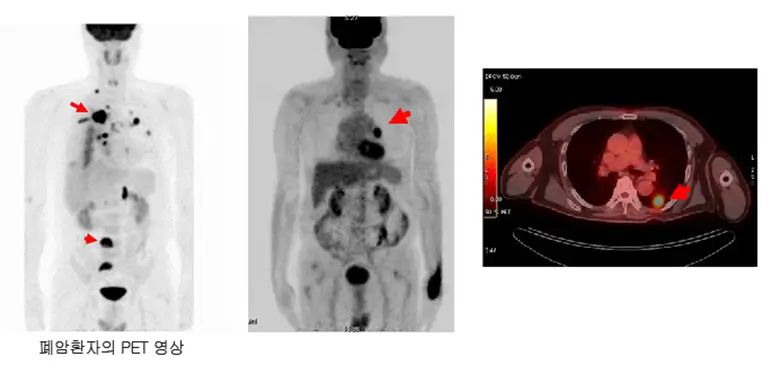

PET-CT

- PET-CT는 암세포의 대사 활동을 평가하여 암의 위치와 전이 여부를 확인하는 데 사용됩니다. 방사성 포도당을 주입하여 암세포의 대사 활동이 활발한 부위를 시각화합니다.

- PET-CT는 전신의 암 전이를 확인하는 데 사용되는 중요한 검사로, 포도당과 유사한 방사성 동위원소를 사용하여 대사 활동이 활발한 암세포를 찾아내고, 전이된 부위를 시각화합니다. 이를 통해 전체 암의 범위를 평가하고, 정확한 병기를 설정할 수 있습니다.